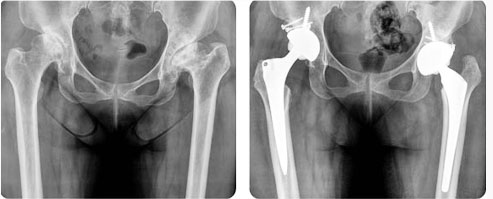

인공 고관절(엉덩이) 치환술이란?

우측 퇴행성 고관절염 및 좌측 선청성 고관절 변형

- 32mm 대형 세라믹 골두 인공 고관절 전치환술 및 자가골 이식술 시행